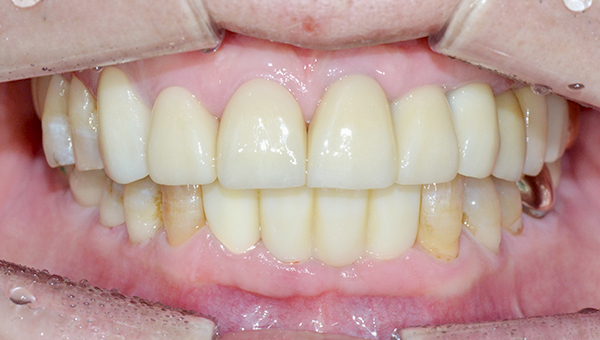

심*복 임플란트 시술 사례

전체 임플란트

2024.12.05

치료 전

2025.05.30

치료 후